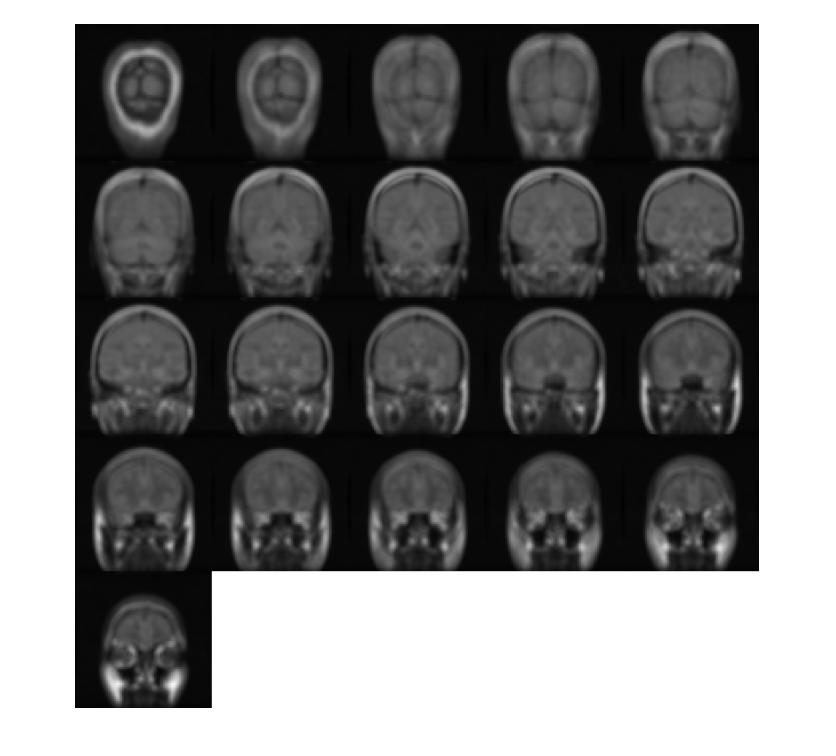

Создайте 3-D фильтр Sobel, который обнаруживает горизонтальные ребра в объеме. Горизонтальные ребра появляются, где существует большая величина градиента в направлении Y, поэтому задайте направление фильтра Sobel как 'Y'. Фильтр Sobel сглаживает градиент в x и z направлениях.

H = fspecial3('sobel','Y');

Отфильтруйте объем с 3-D фильтром Sobel.

edgesHor = imfilter(V,H,'replicate');

Отобразите плоскости отфильтрованного объема.

montage(edgesHor)

Figure contains an axes object. The axes object contains an object of type image.